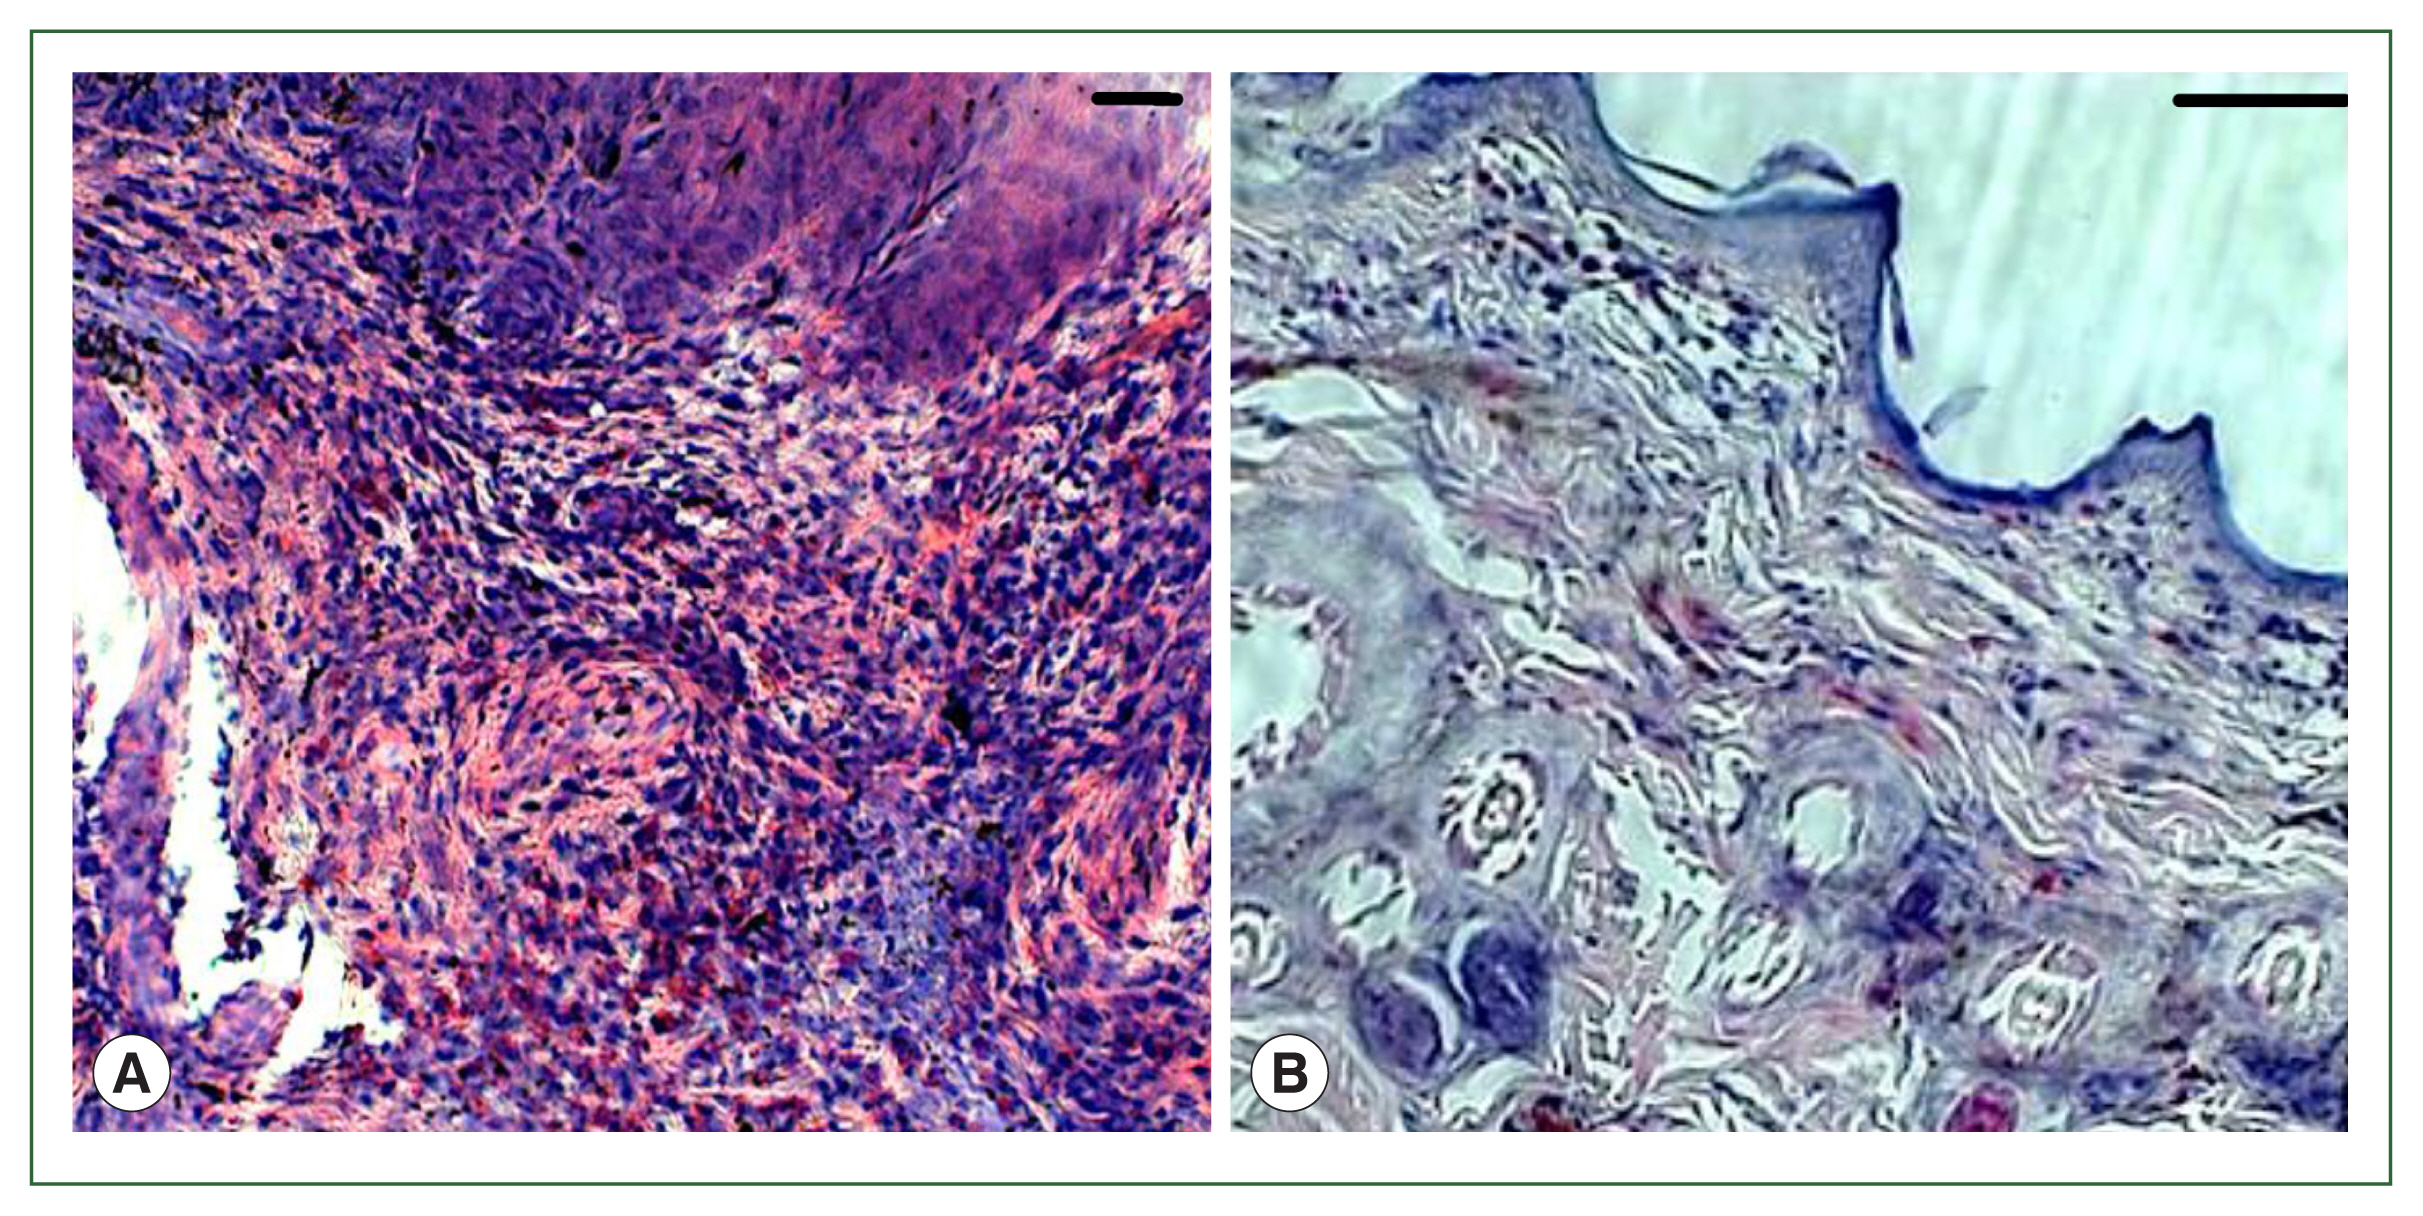

Histopathology

For histological evaluation, skin samples were collected from tick-infested rabbits (3 days post-infestation in histamine-treated rabbits and 6 days post-infestation in antihistamine-treated rabbits) and fixed in a 10% neutral buffered formalin solution. Afterward, fixed tissues were routinely processed [10], embedded in paraffin, and then sectioned at 5-μm thickness using a microtome at room temperature. Tissue sections were stained with hematoxylin and eosin (H & E) and examined under a microscope. Colored images were taken from H & E-stained skin sections using an Olympus BX51 microscope and Olympus DP72 camera equipped with DP2-BSW imaging software (Olympus, Tokyo, Japan).